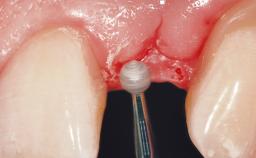

Surgical treatment of a 32-year old, healthy and non-smoking female who required removal and replacement of a lateral maxillary incisor due to internal root resorption. The inflammatory process caused a reduction of the crestal bone level on the distal side of the tooth necessitating an augmentation procedure to meet the patient's high esthetic demands. Due to the high smile line, the thin soft-tissue biotype and triangular-shaped teeth several esthetic risk factors are present.

After flapless tooth removal and a healing period of 6 weeks a diameter-reduced two-piece implant is placed. The bone defect on the facial aspect is corrected with a contour augmentation using autologous bone chips covered with DBBM particles and a collagen membrane according to the Guided Bone Regeneration (GBR) approach.